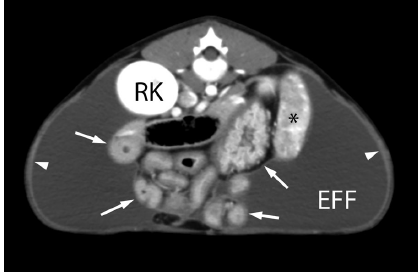

5m Pitty recently spayed and adopted from a shelter presented for recurrent abdominal effusion.

What are your findings? What is your diagnosis?

accumulation of homogeneous soft tissue opaque material within ventral abdomen with dorsal gathering of intestinal tract. Margins of abdominal organs are visualized except for bladder.

Sclerosing encapsulating peritonitis

Imaging diagnosis - sclerosing encapsulating peritonitis in a dog - VRU 2015 - Pre-published

5m Pitty spayed recently and adopted from shelter.

What are your findings? WHat is your diagnosis? Differentials?

Large volume of loculated fluid were noted in ventral abdomen that appeared separte from the abdominal contents (no flaoting or suspension of abdominal organs), Peritoneal lining was thickened.

In this case - trauma or due to spay? Other causes: foreign body ingestion, fiberglass ingestion, bacterial peritonitis, leishmaniasias, asbestos, steatitis, neoplasia

Sclerosing encapsulting peritonitis